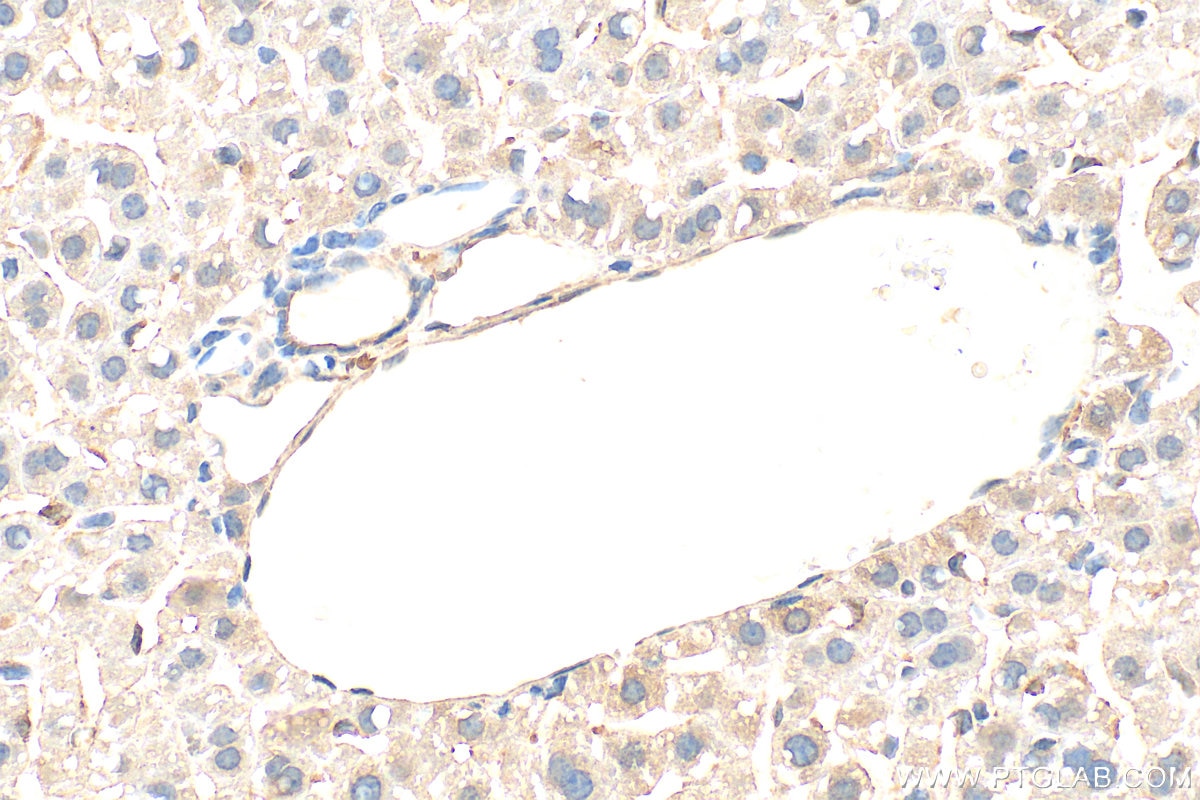

Positive IHC detected inrat liver tissue, mouse liver tissue

Note: suggested antigen retrieval with TE buffer pH 9.0; (*) Alternatively, antigen retrieval may be performed with citrate buffer pH 6.0

Immunohistochemistry (IHC)IHC : 1:250-1:1000